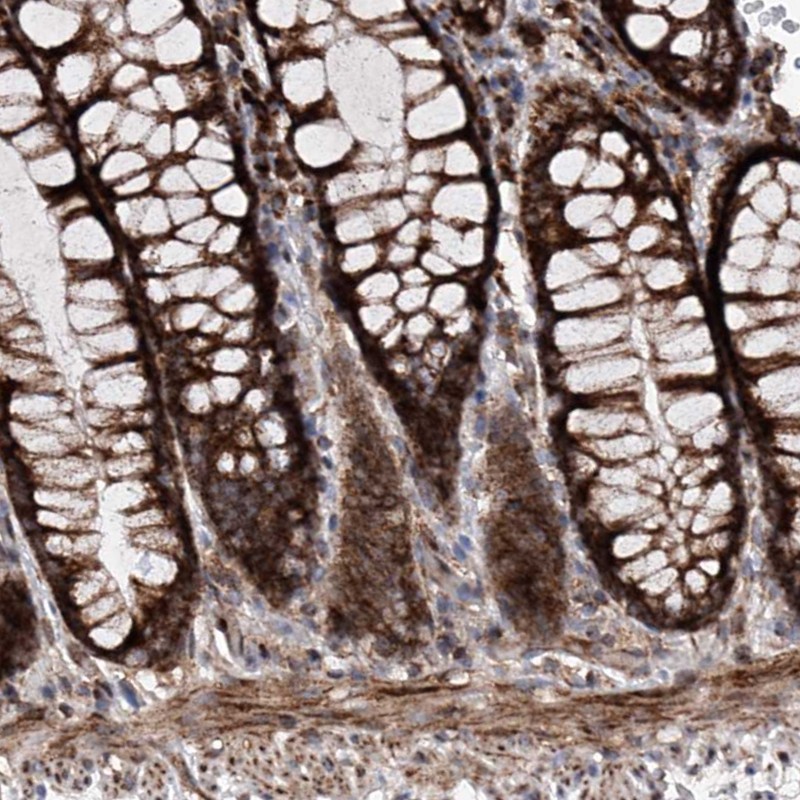

Immunohistochemical staining of human colon shows strong cytoplasmic positivity in glandular cells.